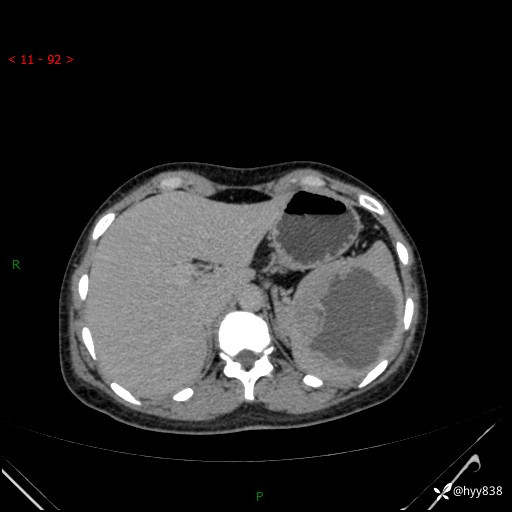

患者性别:男

患者年龄:44岁

主诉:外院超声发现脾脏占位,来我院进一步诊治。

辅助检查:CT

临床诊断:脾脏占位

脾脏CT平扫+增强(动脉期+静脉期)